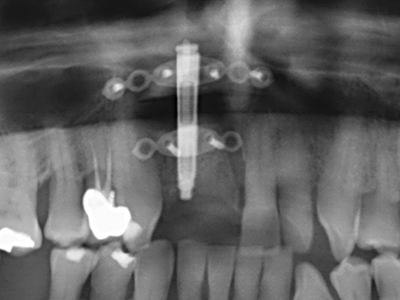

Die Präparation des lateralen Fensters bei der externen Sinusbodenelevation stellt gerade für chirurgisch unerfahrene Implantologen eine große Herausforderung dar. Die knöcherne Bedeckung der Kieferhöhle ohne eine Verletzung der darunterliegenden Schneider’schen Membran abzutragen ist dabei nur ein Teil der Operation – nach Schaffung eines ausreichenden Zugangs muss die Kieferhöhlenschleimhaut vorsichtig mobilisiert werden, um Raum für das einzubringende Material bzw. die Implantate zu schaffen. In dieser Indikation ist die Piezochirurgie zweierlei hilfreich: zum einen kann durch Verwendung diamantierter Instrumente eine selektive Knochenabtragung erfolgen und die darunter liegende Schleimhaut bleibt bei vorsichtiger Vorgehensweise intakt. Zum anderen unterstützen die Ultraschallfrequenzen zusätzlich eine komplikationslose Ablösung der Schleimhaut – sie werden durch spezielle stumpfe Ansätze in den Spaltraum zwischen Schleimhaut und Kieferhöhlenboden übertragen (Cassetta, Ricci et al. 2012, Pereira, Gealh et al. 2014) (Rickert, Vissink et al. 2013). So erscheint es nicht verwunderlich, dass in aktuellen Übersichtsarbeiten über die externe Sinusbodenelevation neben der Verwendung von rauen Implantatoberflächen und dem Einsatz von Knochenersatzmaterialien auch der Einsatz von piezoelektronischen Geräten als positiv bewertet wird (Wallace, Tarnow et al. 2012).

Bei der Knochenblockentnahme zeigen sich weitere Vorteile für die Piezochirurgie: Neben der bereits beschriebenen hohen Präzision bei der Osteotomie stellt sich gerade die Verwendung der dünnen Sägespitzen als besonders materialschonend heraus. Bei der Verwendung insbesondere von Lindemannfräsen sind mit deutlich höheren Entnahmeverlusten durch die dickere Instrumentenspitze zu rechnen (Lakshmiganthan, Gokulanathan et al. 2012). Die insbesondere bei retromolar entnommenen Blocktransplantaten notwendige basale Abtrennung wird durch speziell hierfür vorgesehene rechtwinklige Sägen erleichtert, so dass die Piezochirurgie als präzises, übersichtliches und sicheres Verfahren zur retromolaren Knochenblockgewinnung angesehen wird (Happe 2007) (Abb. 1-12).